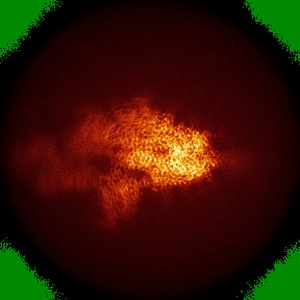

EMD-30516

S protein of SARS-CoV-2 in complex bound with P5A-2G9

Single-particle2.7 Å

Structural basis for bivalent binding and inhibition of SARS-CoV-2 infection by human potent neutralizing antibodies.